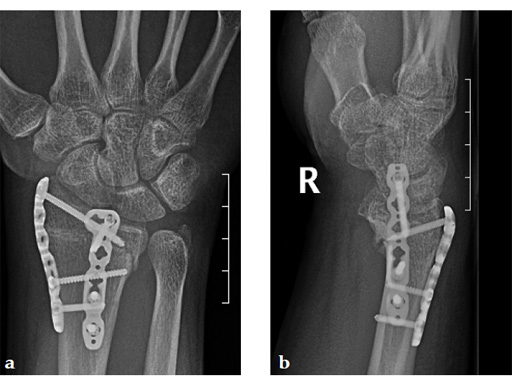

Case 1: A 62-year-old man fell on his outstretched left hand while playing tennis, sustaining an intraarticular fracture of the distal radius, Mller AO Classification 23-C3.2.

Case provided by Renato Fricker, Bruderholz, Switzerland